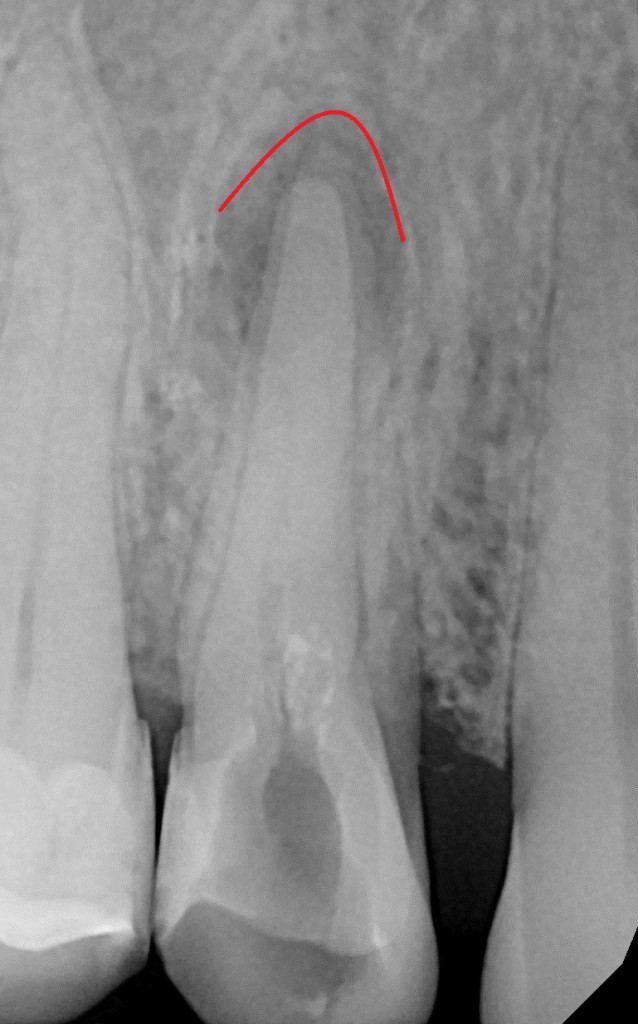

- Malé intraorální rentgenové snímky umožní detailní zobrazení zubů a včasné rozpoznání kazu.